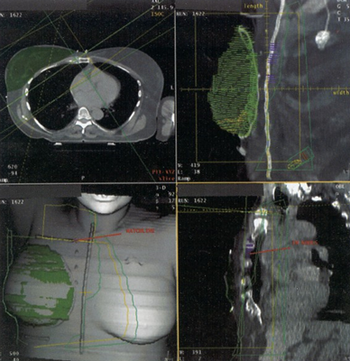

Molecular imaging allows accurate detection of metastatic disease. It also allows for noninvasive assessment of tumors and is a predictor of response to therapy.

However, it is becoming ever clearer that tumor characteristics can change during the course of disease. Given this change over time, other supporting techniques for guiding therapy would be of value. Molecular radionuclide imaging with positron emission tomography (PET) can potentially fulfill this need.

We review how radiolabeled glucose and estrogen analogs can be used in breast cancer patients. We focus this review on the application of positron emission tomography imaging to ER-positive metastatic breast cancer as an example of how imaging can guide breast cancer treatment.